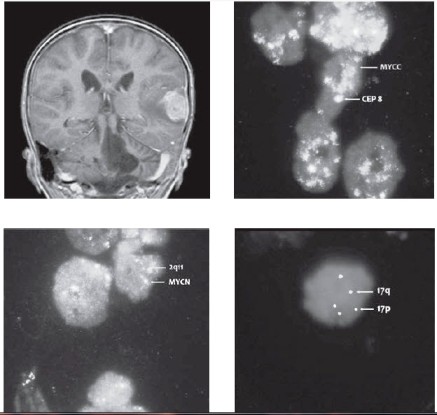

Následovala udržovací léčba kombinací výše uvedeného etoposidu s cykly bioterapie 13-cis retinovou kyselinou. Po 3. cyklu této experimentální léčby MR potvrdilo dosažení 1. kompletní remise onemocnění. Nicméně po krátkém intervalu přichází pacient s příznaky fatické poruchy s váznutím expresivní složky řeči. MRI mozku popsalo recidivu solitární metastázou temporálně vlevo s perifokálním edémem a intenzivním postkontrastním sycením – EFS 13 měsíců (obr. 3). Ložisko bylo radikálně exstirpováno včetně přiléhající tvrdé pleny. Histologicky byla prokázána konverze do anaplastické varianty meduloblastomu s četnými atypickými mitózami, proliferační aktivita dle Ki67 je 70 %. Imunohistochemicky pozitivita synaptophysinu, slabě i chromograninu, fokálně NSE. Tumor změnil i biologické charakteristiky, v metastáze byla potvrzena metodou FISH amplifikace MYCC s více než 50 kopiemi genu, aditivní kopie genu MYCN (3 kopie/2) a izochromosom 17q jako marker delece p53 (obr. 4-6). Operací pacient dosáhl 2. radiologické remise onemocnění. Byla zahájena experimentální paliativní terapie dle protokolu MEMMAT, což je kombinovaná metronomická antiangiogenní léčba (thalidomide, celecoxib, fenofibrate a střídavě nízce dávkovaný perorální etoposid a cyclophosphamide) spolu s intratékalní aplikací etoposidu střídavě s liposomálním cytarabinem.

Nejčastější cytogenetickou odchylkou popisovanou u meduloblastomů jsou abnormity 17. chromosomu (7). Nález isochromozomu 17q (i17q) je spojen se ztrátou funkce tumor-supresorového genu p53 lokalizovaného na 17p. Může se vyskytovat u klasické varianty meduloblastomu a dále v asociaci s amplifikací MYCC a/nebo MYCN u anaplastického/velkobuněčného meduloblastomu (2, 7). Průkaz izo17q je spojen s nepříznivým průběhem onemocnění [7].

Zajímavým fenoménem je konverze méně agresivní varianty meduloblastomu do formy agresivnější při progresi onemocnění. V literatuře nejčastěji popisovanou je změna varianty klasické do A/LC varianty. Konverze desmoplastického meduloblastomu v anaplastický/velkobuněčný typ je raritní. Tuto morfologickou proměnu provází současně kumulace nepříznivých biologických a cytogenetických abnormit, nejčastěji izo17q, amplifikace MYCC či MYCN [8].